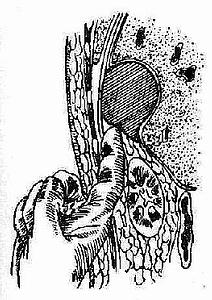

②经后腰部引流途径:此途径适用于左右膈下靠后部的脓肿,即使是右肝上间隙靠后的脓肿,也可采用此引流途径。(图2-41),方法是在局麻下沿第十二肋做切口,在骨膜下切除第十二肋(图2-42),平第一腰椎棘突平面横行切开肋骨床,然后进入腹膜后间隙,用粗针穿刺找到脓腔,再用手指插入脓腔排脓。(图2-43)。手术尽可能在直视下进行,避免误入胸腔。

图2-42 图2-43